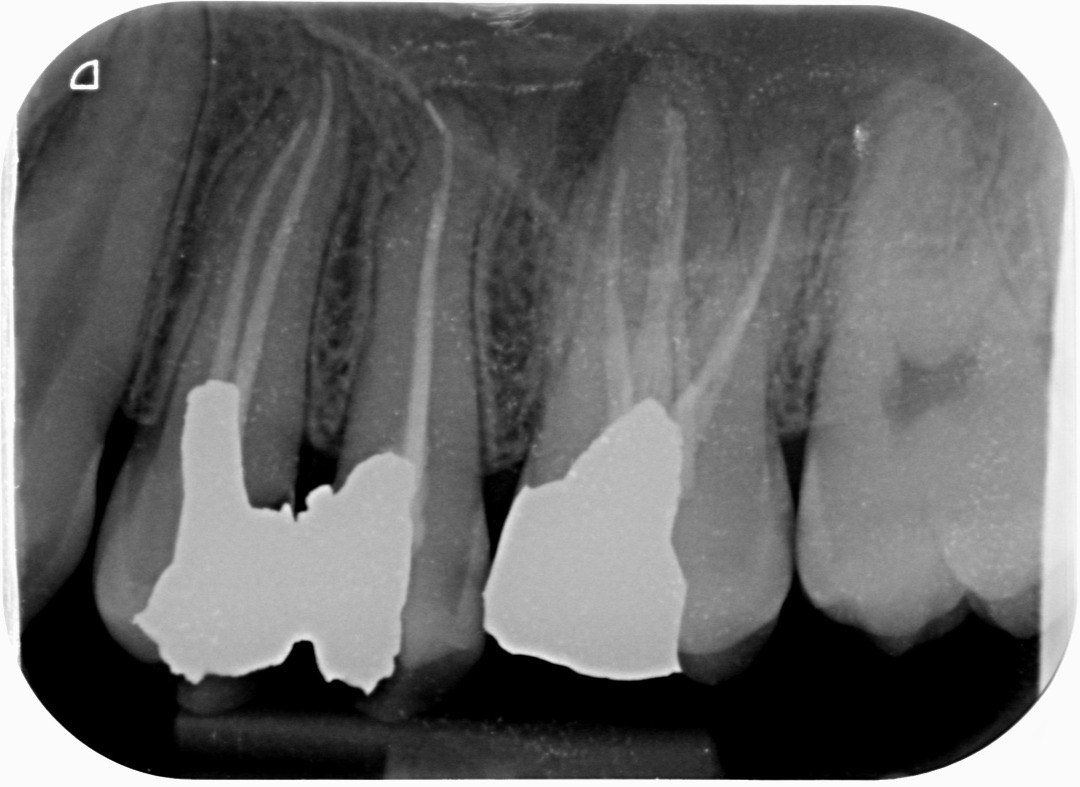

9. Which surfaces shows root caries?

10 / 50

10: What is the caries level on occlusal of the tooth # 2.7?